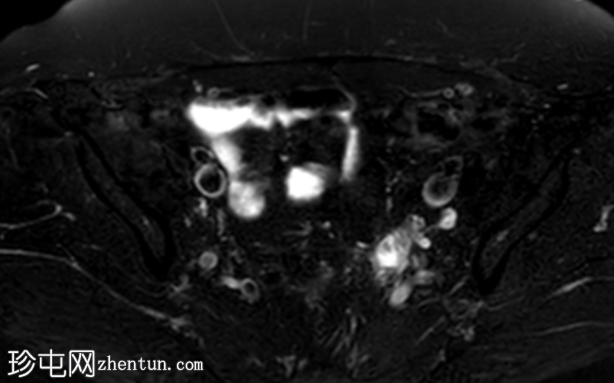

冠状位

T2加权像

盆腔MRI显示左侧骶前区有两个小囊性病变,位于左侧附件的预期解剖位置。

病变在T2加权像上呈高信号,边界清晰,囊壁轻度增厚,光滑。在T1加权脂肪抑制像上,一个病变内部呈高信号,另一个病变呈低信号。静脉注射对比剂后,可见轻度周边囊壁强化,未见强化的实性成分。

未见扩散受限。病灶与邻近盆腔血管关系密切,无周围炎症改变、盆腔淋巴结肿大或游离液体的证据。